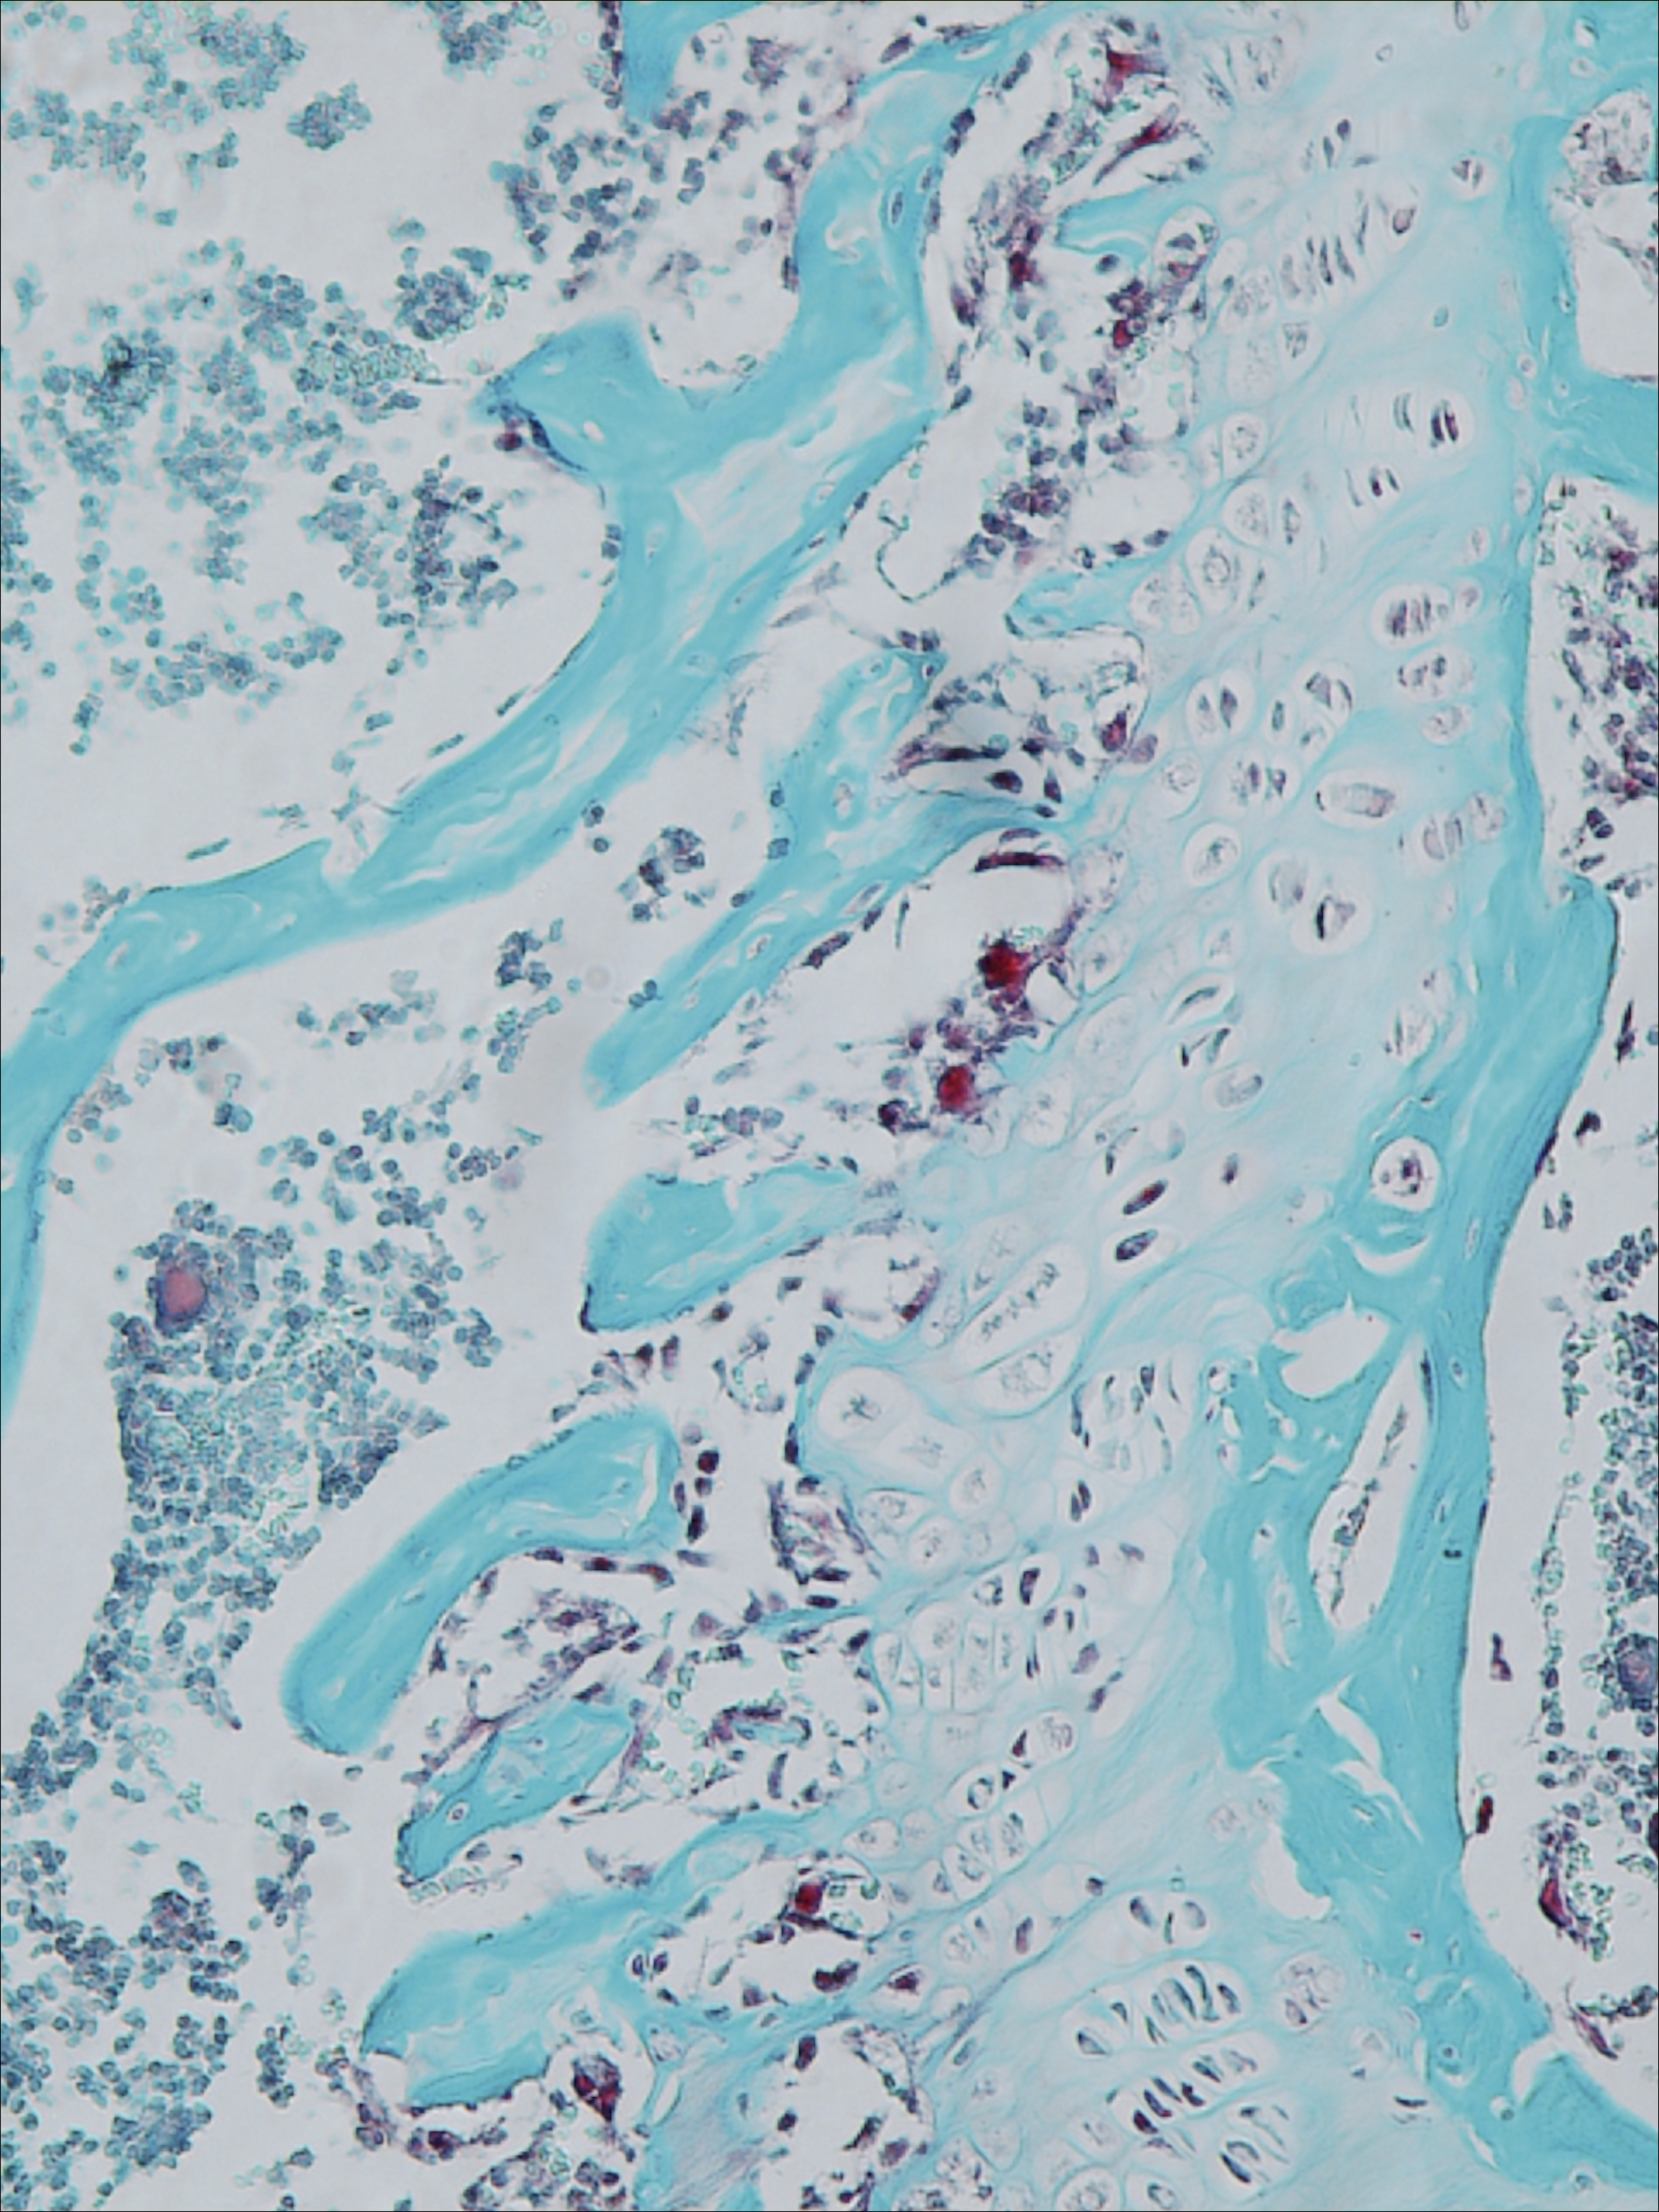

Hemophilic arthropathy (HA) is a major cause of disability in hemophilia A patients. The authors show that tumor necrosis factor-α and its upstream regulators, iRhom2 and ADAM17, have a pivotal role in synovitis and bone loss in HA. This is evidenced by osteoclasts (red) resorbing bone (blue). See the article by Haxaire et al on page 1064.